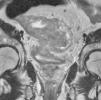

Corte axial donde se observan las capas mucosa (flecha blanca), submucosa (señal propia hiperhintensa) y muscular (flecha negra). Alrededor del recto se encuentra la grasa mesorrectal (GM) y, envolviendo esta grasa, la fascia mesorrectal, visible como una línea hipointensa que rodea todo el paquete graso.

Las capas del recto se aprecian en RM con diferente intensidad de señal. En las secuencias de imagen ponderadas en T2, la mucosa y la muscular aparecen hipointensas, la submucosa hiperintensa. La grasa mesorrectal se muestra hiperintensa y contrasta claramente con la muscular, facilitando en gran medida la observación de una posible infiltración mesorrectal.